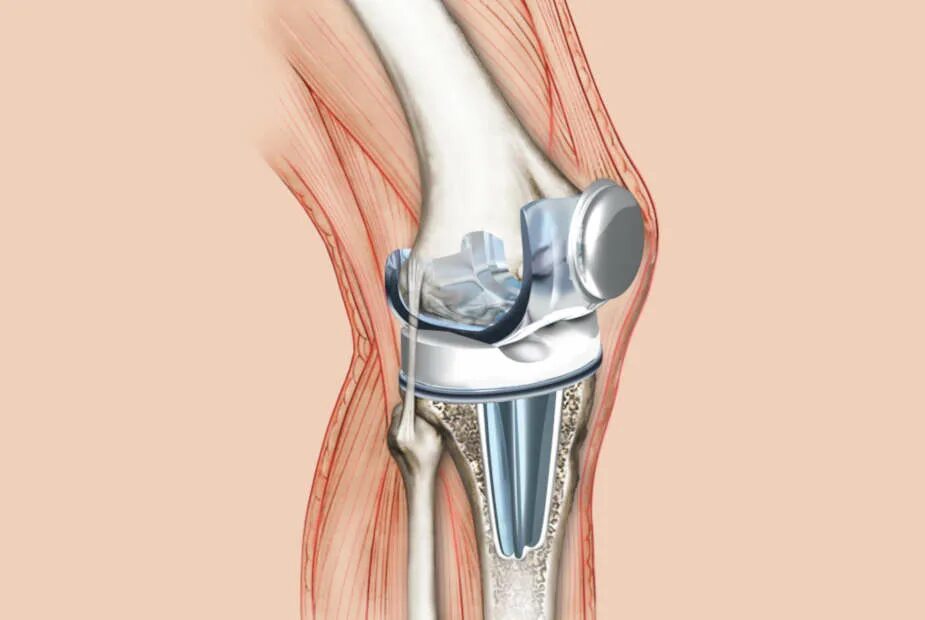

Как делают замену коленного сустава